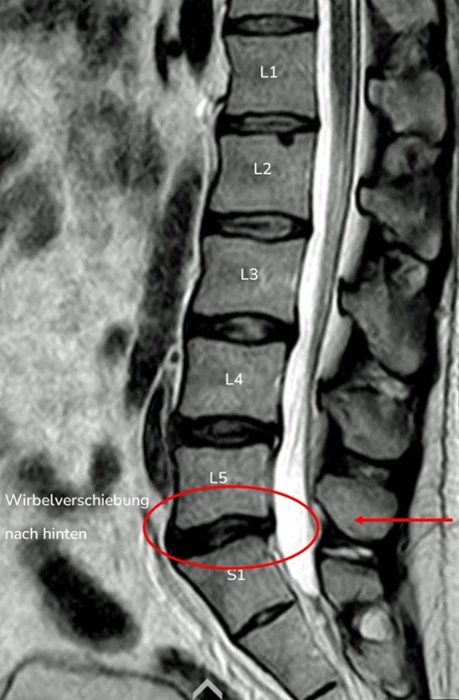

2. Beispiel – Wirbelverschiebung nach hinten

Auch bei dieser Aufnahme kann man Ähnlichkeiten zwischen der MRT-Aufnahme und der Konturdarstellung der Medi Mouse erkennen.

Bei dieser Wirbelsäulenform ist die normale Lordose der Lendenwirbelsäule nicht vorhanden, das Gegenteil ist der Fall, die Kyphose ist bis zum Kreuzbein verlängert.

Dies als Folge einer Rückverlagerung des Oberkörpers, was dazu führt, dass das eine Knicktendenz nach hinten entsteht und die Wirbelverschiebung nach hinten begünstigt.

Bei der Körperhaltungsanalyse kann man sehen, wie die Körpersegmente gegeneinander verschoben sind.

Von unten nach oben:

ist der Unterschenkel nach hinten gekippt

der Oberschenkel nach vorne

das Becken nach vorne verschoben

der Brustkorb gebeugt und nach hinten verschoben

der Schultergürtel und der Kopf nach vorne geschoben

Dieser Haltungstyp entspricht diesem Schema. Man kann sich vorstellen, dass eine solche geknickte Säule an den Knickungsstellen durch das Gewicht der Körpersegmente überlastet werden kann.